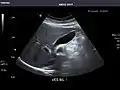

Gallbladder: No stones, wall thickening, or pericholecystic fluid.

Common Bile Duct: Nondilated measuring 1.3 mm at the level of the porta hepatis.

Gallbladder

Bile duct